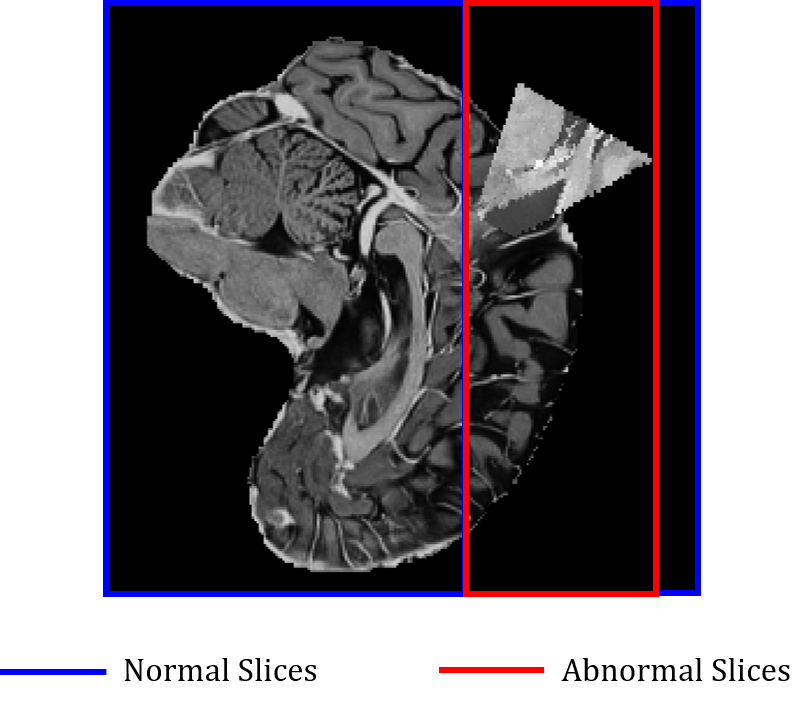

Weighted Binary Cross Entropy Loss. When calculating the similarity loss, it is necessary to consider both the normal image and the abnormal image for a positive pair and a negative pair. However, when both the normal image and the abnormal image are used to determine whether in-distribution or out-of-distribution in a 2D network, a class imbalance problem occurs. This is because the 2D network uses a slice of a volume as an input. A normal volume contains only normal slices, but an abnormal volume contains both normal slices and abnormal slices. In conclusion, normal slice images are overwhelmingly more than abnormal slice images, which hinders network training. Therefore, when computing the classification loss of the 2D network, binary cross entropy is calculated only for slices of abnormal volume. At this time, as shown in Figure 8, there is an imbalance between the normal slice and the abnormal slice even within the abnormal volume. Therefore, in order to improve the learning performance, a weighted binary cross entropy loss that multiplies the abnormal slices by weight is used. This weight is multiplied only on the positive label, and the weight multiplies the ratio of the number of abnormal slices and the number of normal slices. This can be expressed as a formula as follows.

Label Smoothing. Slice images used as input to a 2D network are labeled according to the presence or absence of anomalous pixels in each slice. In this case, even if the slice image contains very small anomalous pixels, such as the boundary between normal and abnormal in the figure 8, it is also classified as an anomaly label. As the number of these input slices increases, it becomes difficult for the 2D network to properly learn classification. Therefore, when the pixels within 3% of the entire slice pixel are abnormal, the label are changed into normal, and when the pixels within 3% to 6% of the slice are abnormal, the label are smoothed to 0.75. If more than 6% of pixels are abnormal, the label is not changed.